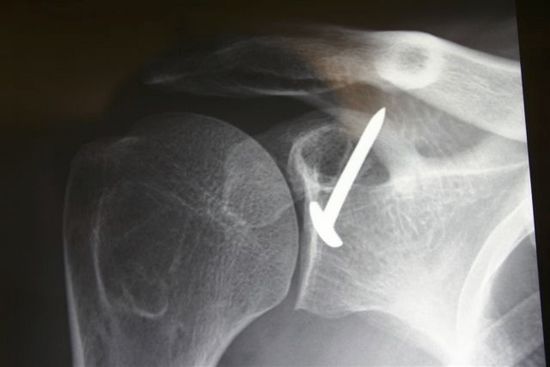

Postoperative anteroposterior X-ray of a right Trillat.

The illustrations demonstrate the effect of the procedure that reduce the coraco-glenoid outlet and lower the subscapularis. Courtesy of Gilles Walch.